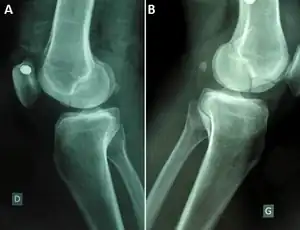

| Segond fracture | Paul Segond | lateral tibial plateau avulsion fracture with anterior cruciate ligament tear | Segond fracture at Who Named It? | ![]() | |